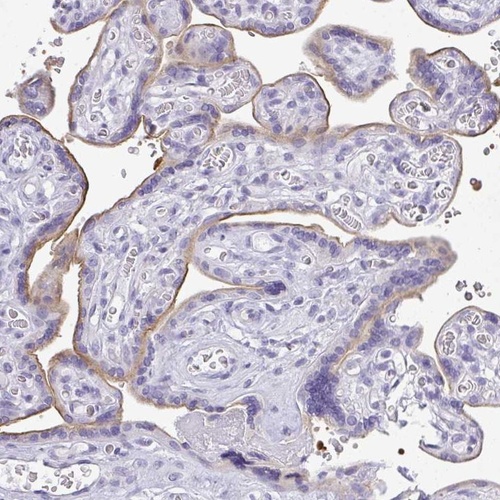

Immunohistochemical staining of human placenta shows moderate membranous positivity in trophoblastic cells.